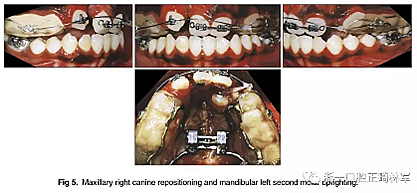

幾個月后,拔除上頜乳尖牙,應(yīng)用0.018×0.025英寸規(guī)格的亞歷山大固定矯治器; 上頜中切牙的對齊由0.014英寸的鎳鈦弓絲開始,而上頜左側(cè)尖牙則是腭側(cè)萌出。在下頜弓中,應(yīng)用舌側(cè)弓和第二前磨牙托槽來實現(xiàn)解除旋轉(zhuǎn)(圖4)。然后,上頜右側(cè)尖牙用0.016英寸的鎳鈦弓絲重新定位,并且使用0.016英寸的不銹鋼片段弓維持中切牙的位置。在下頜弓中,應(yīng)用帶有開放式螺旋彈簧的截面鋼絲直立左側(cè)第二磨牙。它在第一磨牙影響下發(fā)生嚴重傾斜,受到第三磨牙的壓迫(圖5)。如全景片所示,下頜左側(cè)第二磨牙直立得以實現(xiàn)(圖6)。1年后,去除上頜擴弓器,上下牙弓完全吻合。在上下牙弓中,用0.017×0.025英寸的鎳鈦弓絲進行整平。上頜左側(cè)尖牙被移至側(cè)切牙位置; 下頜第一前磨牙被拔除,尖牙開始縮回。